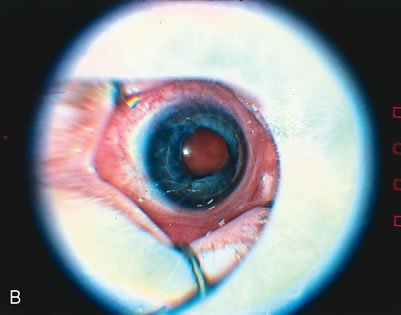

threshold retinopathy of prematurity. Arch Ophthalmol 119:615, 2001 51. Rundle P, McGinnity FG: Bilateral hyphaema following diode laser for retinopathy of prematurity. Br J Ophthalmol 79:1055, 1995 52. Simons BD, Wilson MC, Hertle RW, Schaefer DB: Bilateral hyphemas and cataracts after diode laser retinal photoablation

for retinopathy of prematurity. J Pediatr Ophthalmol Strabismus 35:185, 1998 53. Capone A Jr, Drack AV: Transient lens changes after diode laser retinal photoablation for retinopathy

of prematurity. Am J Ophthalmol 118:533, 1994 54. Drack AV, Burke JP, Pulido JS, Keech RV: Transient punctate lenticular opacities as a complication of argon laser

photoablation in an infant with retinopathy of prematurity. Am J Ophthalmol 113:583, 1992 55. Pogrebniak AE, Bolling JP, Stewart MW: Argon laser-induced cataract in an infant with retinopathy of prematurity. Am J Ophthalmol 117:261, 1994 56. Lambert SR, Capone A Jr, Cingle KA, Drack AV: Cataract and phthisis bulbi after laser photoablation for threshold retinopathy

of prematurity. Am J Ophthalmol 129:585, 2000. 57. Noonan CP, Clark DI: Acute serous detachment with argon laser photocoagulation in retinopathy